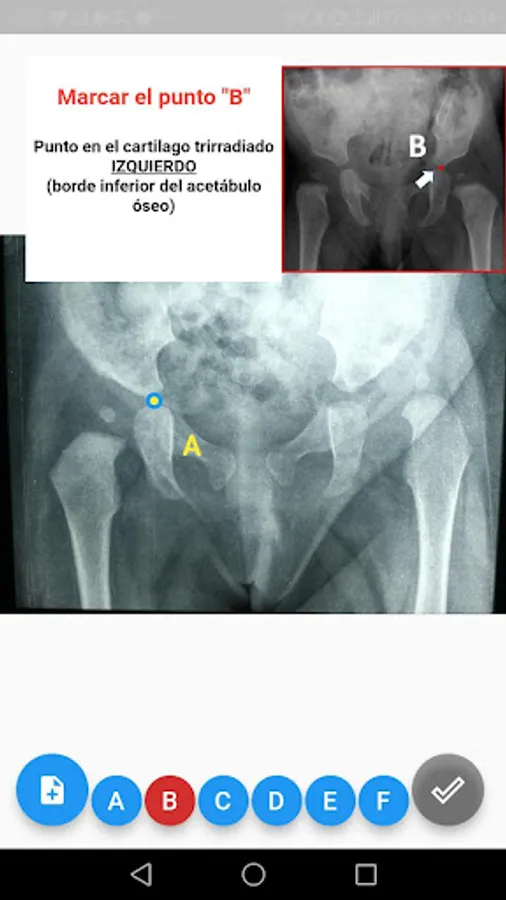

5. Start the marking by pressing the icon with the letter "A", follow the instructions in the box and the image provided. Subsequently, you can pass icons B, C, D, E, F consecutively.

6. It is possible to press any of the icons (A, B, C, D, E, F) and modify the points in case it is necessary to change the initial marking.